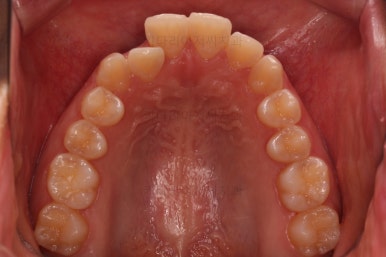

초진 시 입안의 모습이에요. 치열이 많이 나쁜 편은 아니고 앞니쪽이 조금 삐뚤어져 있네요.

특히 윗니 작은 앞니 하나가 아랫니보다 안으로 쑥 들어가 있어서 옆에 있는 송곳니가 덧니처럼 보여요.